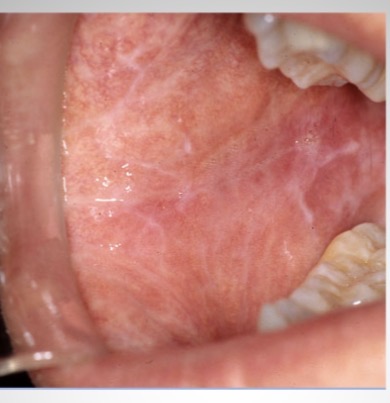

What is this condition?

Lichen planus

-note lacelike Wickman's striae

-autoimmune disorder precipitated by STRESS